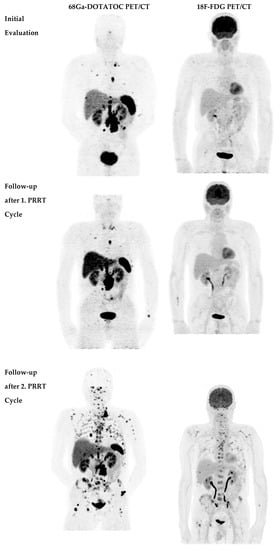

2.2. Disease Course after Second PRRT Course

- Nilica, B.; Waitz, D.; Stevanovic, V.; Uprimny, C.; Kendler, D.; Buxbaum, S.; Warwitz, B.; Gerardo, L.; Henninger, B.; Virgolini, I.; et al. Direct comparison of 68Ga-DOTA-TOC and 18F-FDG PET/CT in the follow-up of patients with neuroendocrine tumour treated with the first full peptide receptor radionuclide therapy cycle. Eur. J. Nucl. Med. Mol. Imaging 2016, 43, 1585–1592. [Google Scholar] [CrossRef]